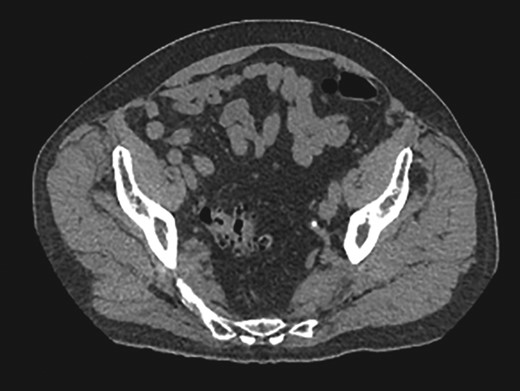

A 77-year-old male with a past medical history of coronary artery disease presented to the emergency department with right lower quadrant pain associated with constipation and nausea for 2 days. The patient did not have any prior episodes of these symptoms or any previous abdominal surgeries. Physical exam revealed right lower quadrant tenderness. The patient underwent computed tomography of the abdomen and pelvis, which showed diverticulosis and a 5.7 cm AAA. Additionally, it showed a right inguinal hernia containing bowel (Fig. 1). The patient’s symptoms resolved after analgesics and fluid resuscitation. The patient then followed up outpatient for the hernia and was booked for an elective robotic repair.